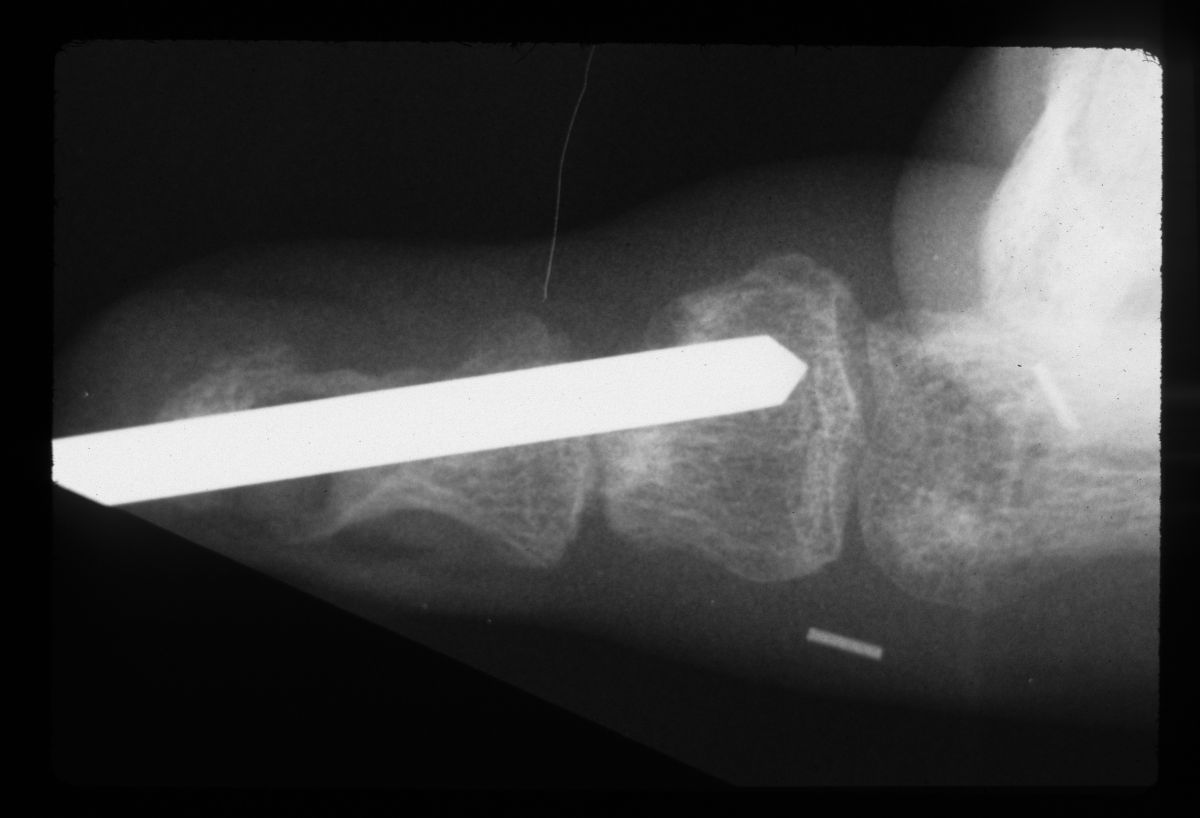

| The graft was sculpted to the diameter of a Steinmann pin. |

| That pin was used as a drill and then replaced with the bone graft. The cyst defect was packed with cancellous bone. |

| After tapping the bone graft into place. |